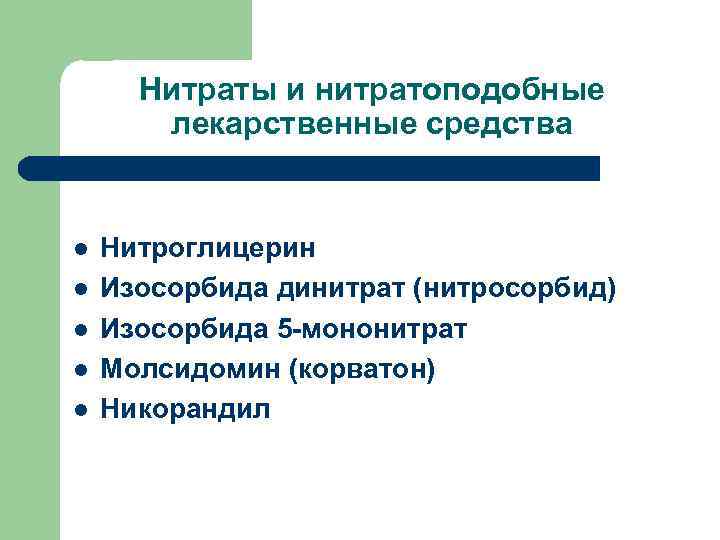

Нитраты и нитратоподобные лекарственные средства l l l Нитроглицерин Изосорбида динитрат (нитросорбид) Изосорбида 5 -мононитрат Молсидомин (корватон) Никорандил